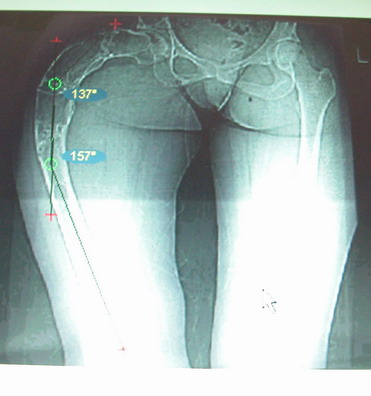

Моё мнение, что двойная остеотомия бедра с аппаратом Илизарова + Гексаподный механизм, или Тэйлора, В данной ситуации является методом выбора. Я очень извеняюсь за качество прилагаемых снимков, в которых я постарался отразить разницу междe одной и двумя остеотомиями бедра.

jo> отразить разницу межде одной и двумя остеотомиями бедра.

Скорее всего, второй уровень может оказаться нелишним лишь при переходе с аппарата на интрамедуллярный стержень. И его не поздно будет пересечь именно в момент введения гвоздя, если будет угроза перфорации стенки канала.

Если сделать фото больного после устранения деформации, вряд ли удастся догадаться, на скольких уровнях она устранялась.